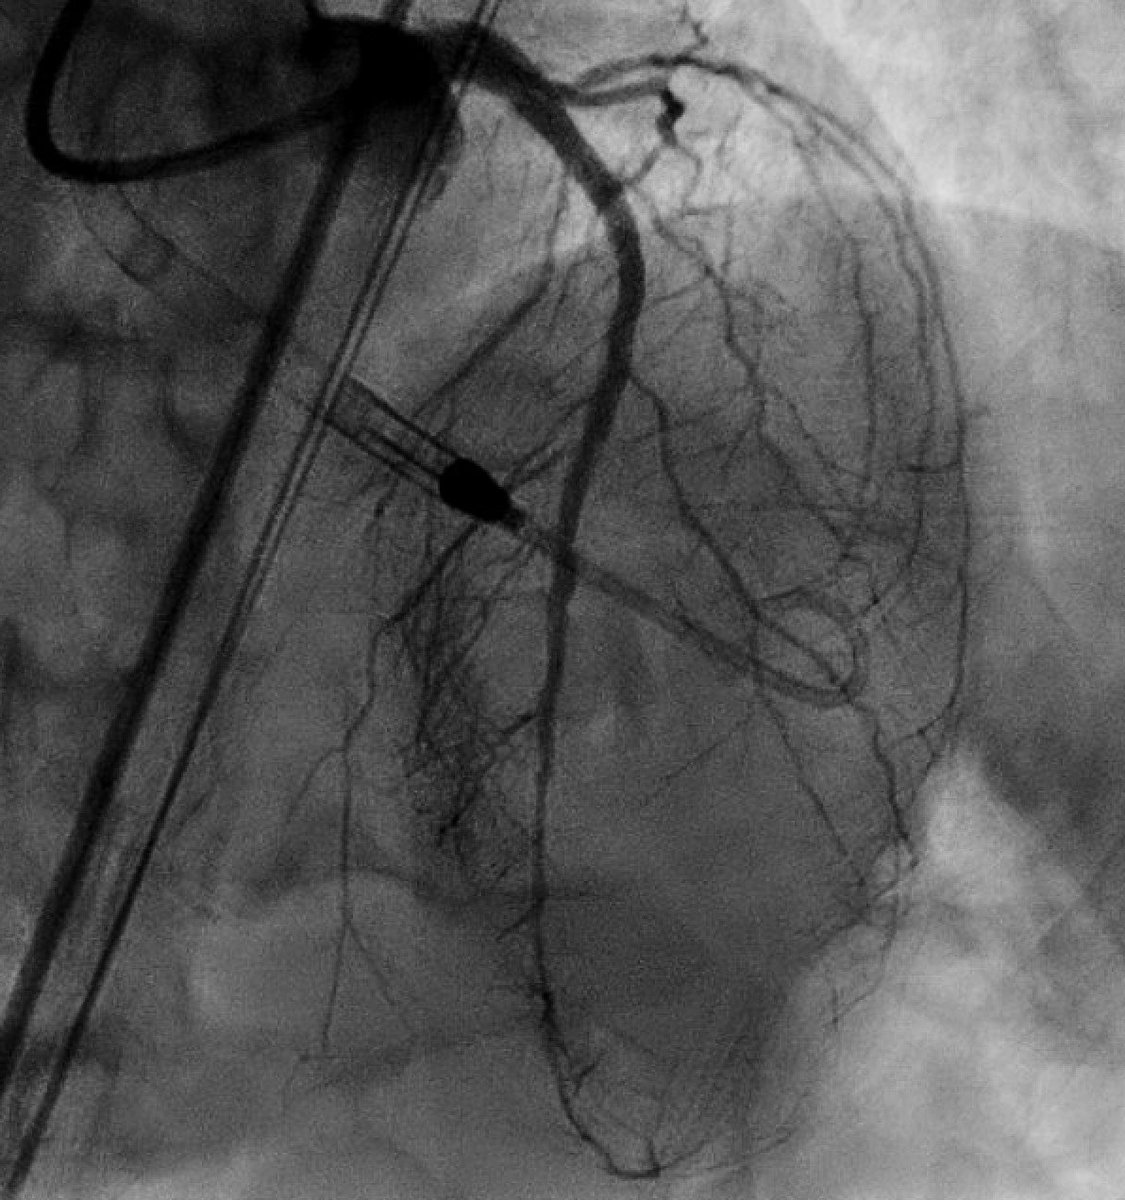

42 year old man, with a PMHx of HTN and HLD, who experienced chest pain but only came to the hospital at his wife’s behest. Time and again, we are reminded why married men have better cardiovascular outcomes: ahajournals.org/doi/full/10.11… #Cardiotwitter #InterventionalCardiology